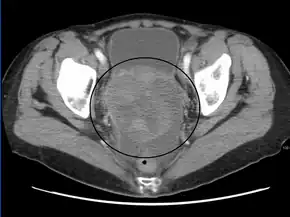

CT scanning is preferred to assess the extent of the tumor in the abdominopelvic cavity, though magnetic resonance imaging can also be used.[28] CT scanning can also be useful for finding omental caking or differentiating fluid from solid tumor in the abdomen, especially in low malignant potential tumors. However, it may not detect smaller tumors. Sometimes, a chest x-ray is used to detect metastases in the chest or pleural effusion. Another test for metastatic disease, though it is infrequently used, is a barium enema, which can show if the rectosigmoid colon is involved in the disease. Positron emission tomography, bone scans, and paracentesis are of limited use; in fact, paracentesis can cause metastases to form at the needle insertion site and may not provide useful results.[29] However, paracentesis can be used in cases where there is no pelvic mass and ascites is still present.[29] A physician suspecting ovarian cancer may also perform mammography or an endometrial biopsy (in the case of abnormal bleeding) to assess the possibility of breast malignancies and endometrial malignancy, respectively. Vaginal ultrasonography is often the first-line imaging study performed when an adnexal mass is found. Several characteristics of an adnexal mass indicate ovarian malignancy; they usually are solid, irregular, multilocular, and/or large; and they typically have papillary features, central vessels, and/or irregular internal septations.[31] However, SCST has no definitive characteristics on radiographic study.[33]

In advanced cancers, where complete removal is not an option, as much tumor as possible is removed in a procedure called debulking surgery. This surgery is not always successful, and is less likely to be successful in women with extensive metastases in the peritoneum, stage- IV disease, cancer in the transverse fissure of the liver, mesentery, or diaphragm, and large areas of ascites. Debulking surgery has usually only been done once[28] but a recent study has shown a longer overall survival in recurrent ovarian cancer when surgery combined with chemotherapy was performed compared to treatment with chemotherapy alone.[97] Computed tomography (abdominal CT) is often used to assess if primary debulking surgery is possible, but low certainty evidence also suggests fluorodeoxyglucose‐18 (FDG) PET/CT and MRI may be useful as an addition for assessing macroscopic incomplete debulking.[98] More complete debulking is associated with better outcomes: women with no macroscopic evidence of disease after debulking have a median survival of 39 months, as opposed to 17 months with less complete surgery.[26] By removing metastases, many cells that are resistant to chemotherapy are removed, and any clumps of cells that have died are also removed. This allows chemotherapy to better reach the remaining cancer cells, which are more likely to be fast-growing and therefore chemosensitive.[29]